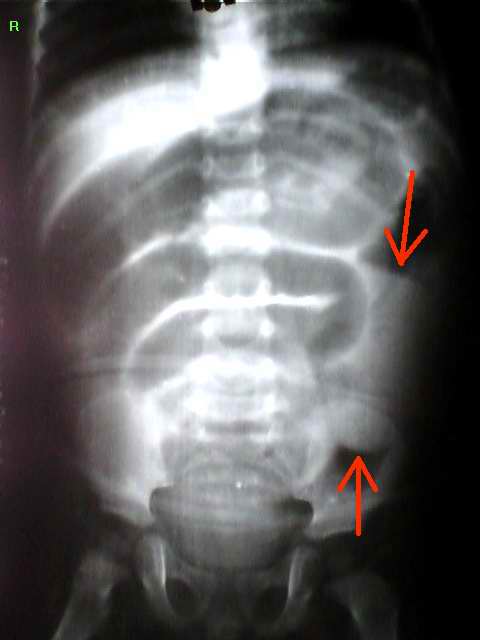

术后诊断:肠套叠。术中所见:腹腔有少量淡血性液体,全小肠充气,轻度发绀。腹腔左侧探及蜡肠样肠管约12厘米,重度发绀。

肠套叠中一重要征象是套叠肿块征。由于受到套叠发生、发展及回盲部系膜的影响,套叠肿块可位于右上腹、腹中部、左腹、甚至下腹部。本例套叠肿块位于左腹(红箭头标示)。